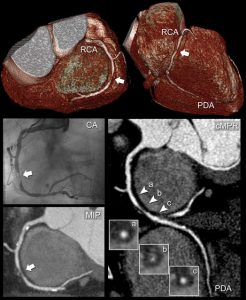

Έτσι η ιστορία της αξονικής στεφανιογραφίας, που ξεκίνησε από την περιγραφή του αυλού και την ανατομία, εξελίχθηκε στον χαρακτηρισμό της αθηρωματικής πλάκας και τη γνώση των χαρακτηριστικών της υψηλού κινδύνου πλάκας. Γνωρίζουμε επίσης ότι μπορούμε να επέμβουμε φαρμακευτικά, με τη μεγαλύτερη αξία να έχουν οι στατίνες, που αποτελούν φάρμακα αντιλιπιδαιμικής αγωγής, αυξάνοντας την επασβέστωση του νεκρωτικού πυρήνα της αθηρωματικής πλάκας και καθιστώντας την πιο σταθερή. Ήδη το 2007 ο Μotoyama περιέγραψε τα χαρακτηριστικά της υψηλού κινδύνου αθηρωματικής πλάκας, της πλάκας που, ανεξαρτήτως του βαθμού στένωσης, μπορεί να προκαλέσει οξέα συμβάματα, όπως οξύ έμφραγμα και καρδιακό θάνατο. (4)

Παράδειγμα μη αποφρακτικής αθηρωματικής πλάκας υψηλού κινδύνου